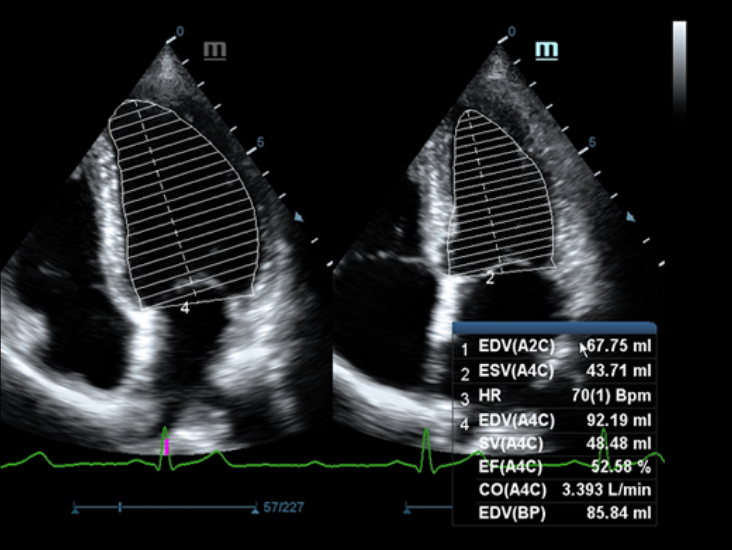

X-Insight adalah solusi untuk visualisasi lebih lanjut.

Sebagai mitra yang menyeluruh, DC-60 Exp dengan X-Insight memfokuskan dirinya untuk menghadirkan solusi yang komprehensif untuk membantu Anda mengelola semua aspek praktik klinis harian dengan mudah dan baik.

Dengan pemahaman mendalam atas kebutuhan pelanggan, DC-60 Exp dengan X-Insight dirancang untuk menyajikan efisiensi tinggi dengan pencitraan yang presisi, yang didukung oleh eXpress Clarity, eXceptional Intelligence, dan eXceeding Experience.